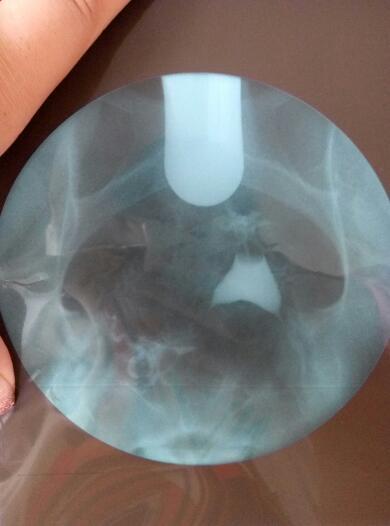

帮我看看,什么情况,还能自然受孕吗?不做手术吃药能解决吗?好人一生平安 点击展开 匿名用户 2016-06-01 09:40 满意回答 根据你的输卵管造影检丛遮查结果显示,筝扬露应该考虑是属于输卵管阻塞等原因引起的症且脑状,应该是比较难自然受孕的,应该积极进行治疗。可以考虑进行输卵管通水治疗的。必要时可以考虑进行宫腔镜,三镜一丝等手术治疗。 太阳荣华医师 2016-06-01 10:03 宝宝知道提示您:回答为网友贡献,仅供参考。 相关问题 请问这是什么?好人一生平安帮我看看吧 朋友们懂得人帮我看看,像这样的报告我想做人工受孕的机率大吗? 一个朋友结婚四年多了,他老婆不孕 现在医院要她做手术治疗 先吃了催排药打算现让他们试一个月自然受孕